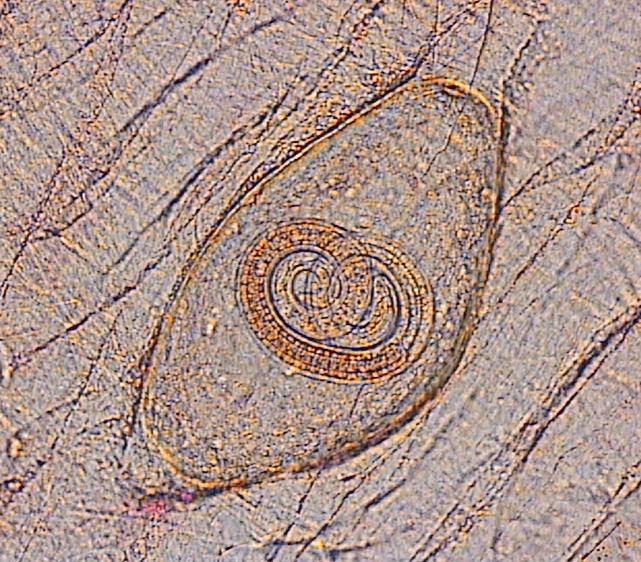

ajifyzb0b307al0upov2.jpg

شکل چشم آدمها هم هست.........